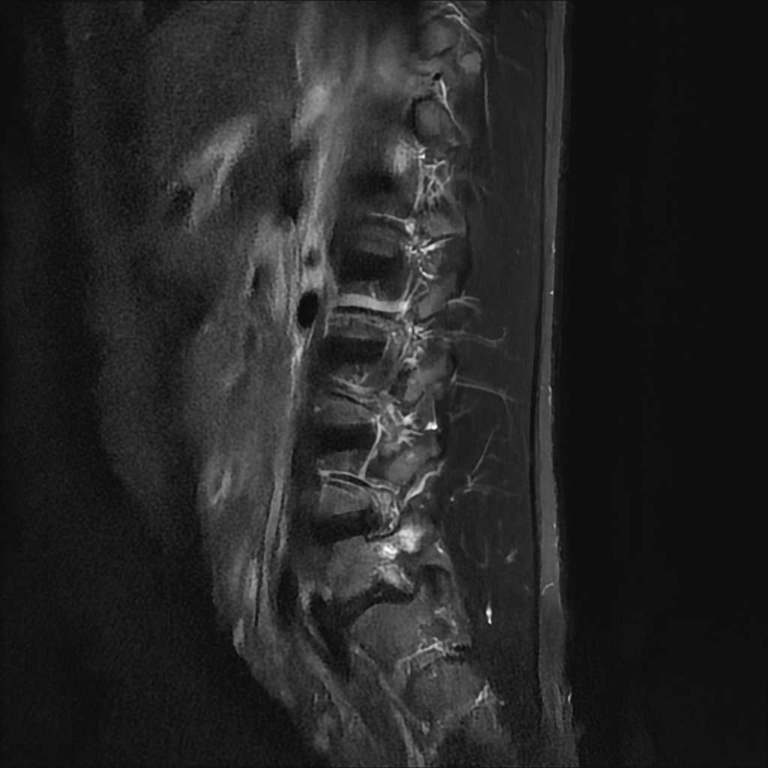

整形外科領域

脊椎

椎間板ヘルニア

圧迫骨折

分離症